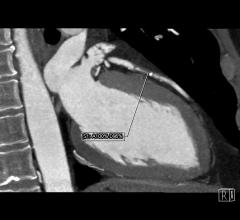

March 19, 2015 — Use of computed tomography coronary angiography (CTA), which provides 3-D images of the heart, coupled…

March 16, 2015 — Results from the PROMISE clinical trial confirmed what many cardiologists and radiologists have long…